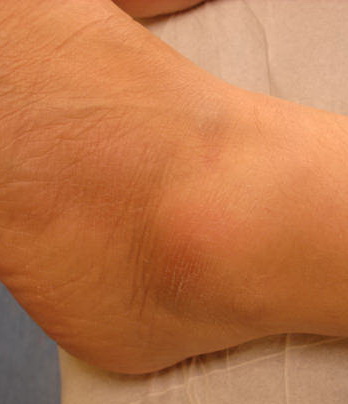

Sarcoidosis = الساركوئيد